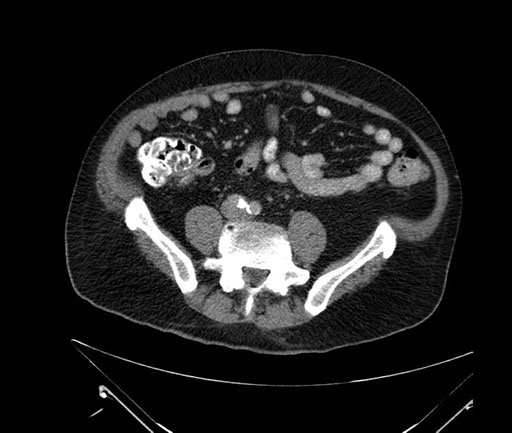

Imaging Analysis

Look through the patient's CT scan to identify any areas of concern for the necessary procedure.

Based on your CT findings, which issue(s) would give reason for "planned slowing down moment(s)" in this case?